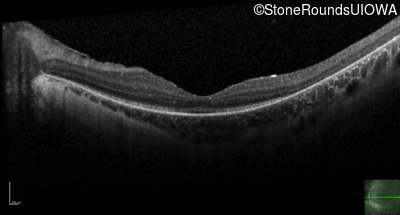

Age at visit: 16 years

This 16 year old female has had poor visual acuity and poor vision in dim light for most of her life. She has normal hearing and no cognitive difficulties.

SECORD RPE65 IVS1+5 G>A Arg124Stop CGA>TGA AR